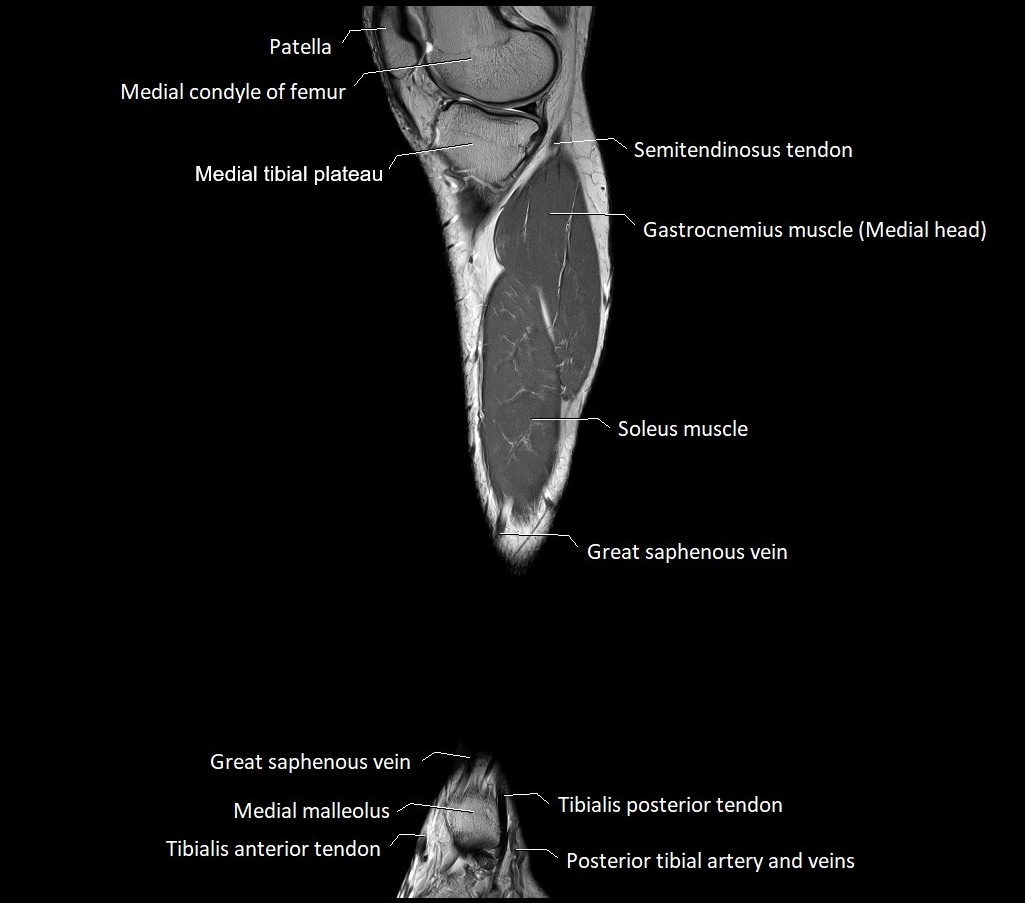

MRI image